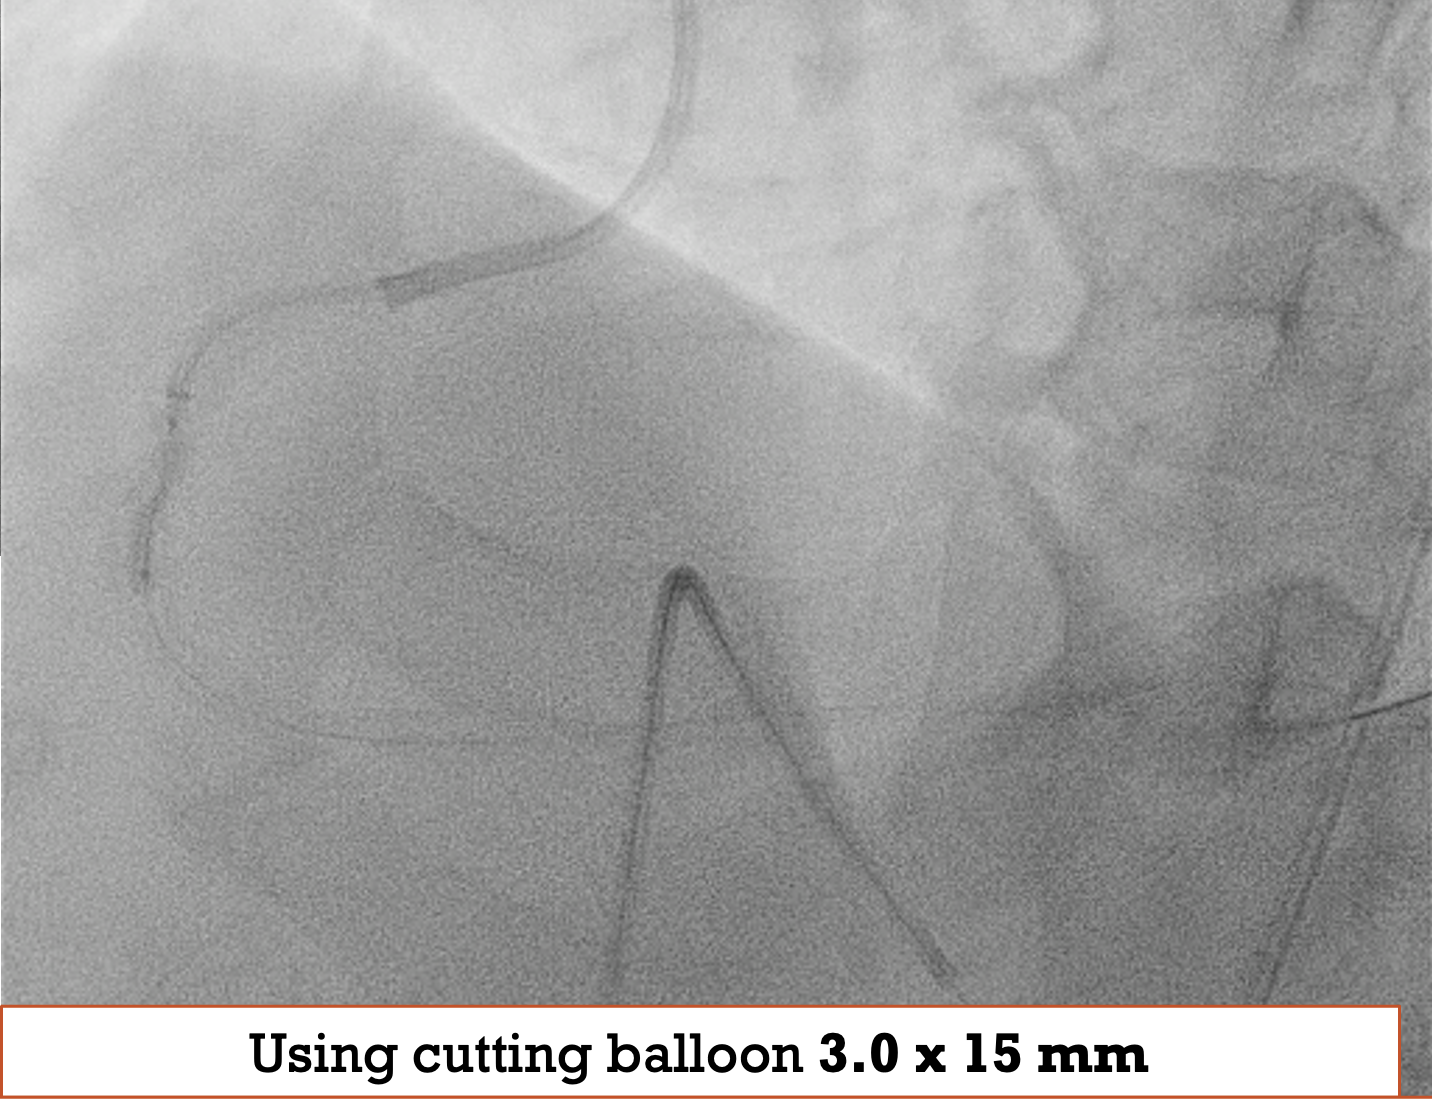

PCI to RCA : Canulation using guiding catheter AL 0.75/7Fr, heparin was administered. Workhorse wire to distal PL. Initial attempt with a 1.5 ¡¿ 15 mm balloon failed to cross the distal lesion and subsequently ruptured. Rotational atherectomy was performed using a 1.5 mm burr at 160–180k rpm with three runs and one polishing pass. A 2.0 ¡¿ 15 mm semi-compliant balloon was then advanced from distal to proximal segments with the assistance of a guide extension catheter.IVUS evaluation demonstrated a 360¡Æ circumferential calcium arc and multiple calcium nodules extending from proximal to distal RCA. Lesion preparation was continued using sequential scoring balloon 2.0 mm and NC 2.5 mm, and cutting balloon 3.0 mm at high pressure. A ¡°dogbone¡± appearance was noted with the cutting balloon at the proximal RCA. An intravascular lithotripsy (IVL) balloon 3.0 mm was then applied to both distal and proximal RCA, delivering a total of 120 pulses (up to 8 atm).Repeat IVUS confirmed adequate calcium modification and optimal lesion preparation. Three overlapping drug-eluting stents (DES) were deployed: 3.0 ¡¿ 38 mm (distal–mid RCA), 3.5 ¡¿ 32 mm (mid RCA), and 4.0 ¡¿ 22 mm (ostial–proximal RCA), followed by sequential post-dilatation up to 4.0 mm. Final IVUS confirmed good stent apposition and expansion, with a minimal stent area of 6.36 mm©÷ at the distal RCA. TIMI 3 flow was achieved. Total contrast volume: 160 mL, Fluoroscopy time: 01:09:34 minutes, DAP: 232 Gy¡¤cm©÷